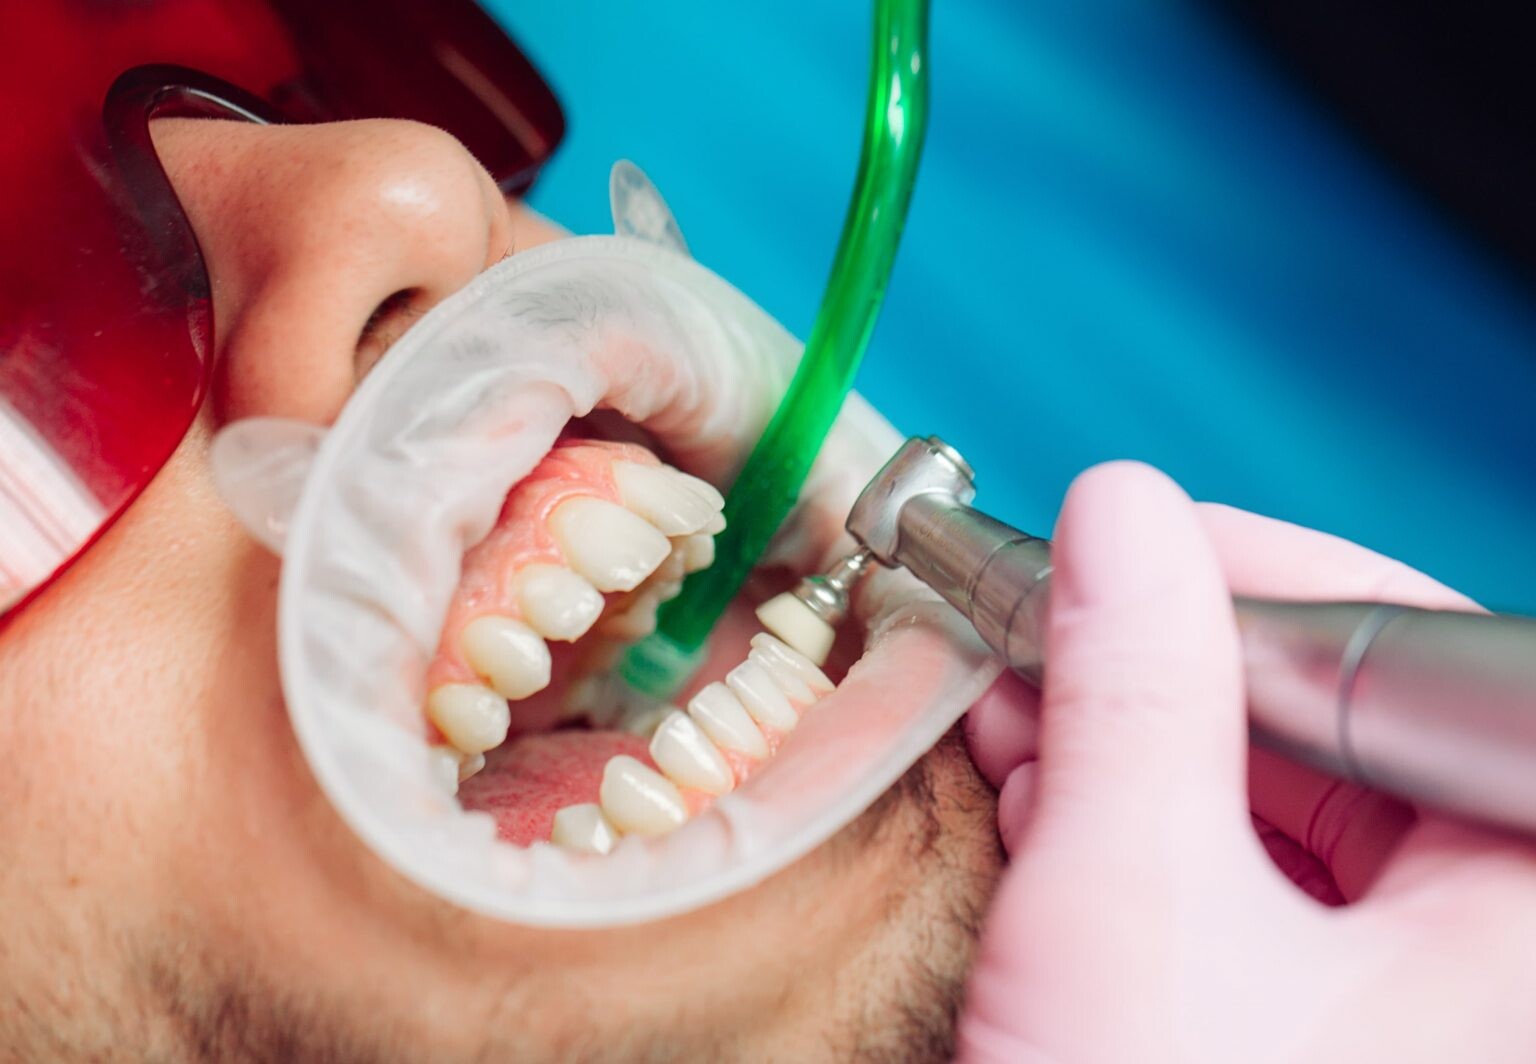

Regularly scheduled dental cleanings are crucial in keeping your teeth and gums healthy.

A prophylaxis treatment is a technical term for regular teeth cleaning. Prophylaxis appointments and proper at-home oral care can contribute to a radiant smile and overall well-being.

This article explores what dental cleaning entails, and what you can expect during a prophylaxis session.

Prophylaxis dental cleaning, is a preventive dental procedure to remove plaque, tartar, and stains from the teeth and gums.

Prophylaxis dental cleaning is an essential part of maintaining optimal oral health.

This procedure is typically performed by a dental hygienist or a dentist in a dental office.

Is Prophylaxis the Same as Teeth Cleaning?

Yes, prophylaxis is a dental term for regular teeth cleaning and involves the removal of plaque and tartar.

Dental scaling and root planing is a more intensive procedure to treat gum disease. It involves cleaning below the gum line and smoothing the tooth roots to eliminate bacteria and promote gum healing.

On the other hand, regular dental cleaning is a preventive measure that focuses on maintaining oral health and preventing the progression of gum disease.

It is generally recommended for individuals with healthy gums and serves as a routine cleaning to remove plaque and tartar buildup.

What is Done During a Dental Prophylaxis Session?

A dental prophylaxis session usually involves several steps to ensure thorough cleaning of your teeth and gums.

During a teeth cleaning appointment, you can expect the following procedures:

Examination: The dental professional will comprehensively examine your mouth before the cleaning begins. This examination helps identify oral health issues and determine the appropriate treatment plan.

Plaque and Tartar Removal: Using specialized dental instruments, the dental hygienist or dentist will carefully remove plaque and tartar deposits from your teeth. They will focus on areas that are hard to reach during regular brushing and flossing.

Teeth Polishing: After plaque and tartar removal, the dental professional will polish your teeth using a rotating brush or a rubber cup with an abrasive paste. This step helps remove surface stains and leaves your teeth looking clean and shiny.

Flossing and Rinsing: Once the teeth are polished, they will floss between your teeth to remove any remaining debris or plaque. They may also ask you to rinse your mouth to remove any residual polishing paste or debris.